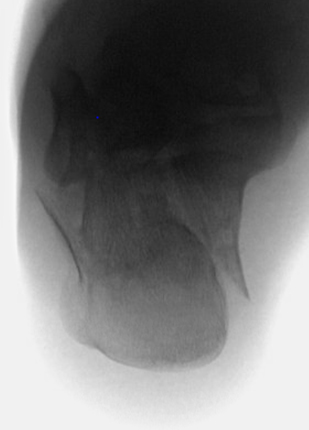

TOTAL ANKLE REPLACEMENT :: ORIF CALCANEUS :: ORIF ANKLE FRACTURE DISLOCATION :: COMPLEX BUNION AND LESSER TOE CORRECTION :: TALUS FRACTURE -1 :: TALUS FRACTURE -2 :: LISFRANC REPAIR :: COMPLEX TRIPLE ARTHRODESIS 1 :: COMPLEX TRIPLE ARTHRODESIS 2 :: MINIMALLY INVASIVE BUNION REPAIR 1 :: MINIMALLY INVASIVE BUNION REPAIR 2 :: ARTHROSCOPIC CARTILAGE REPAIR :: TENEX SPUR DEBRIDEMENT :: Haglunds Debridement and Achilles Repair